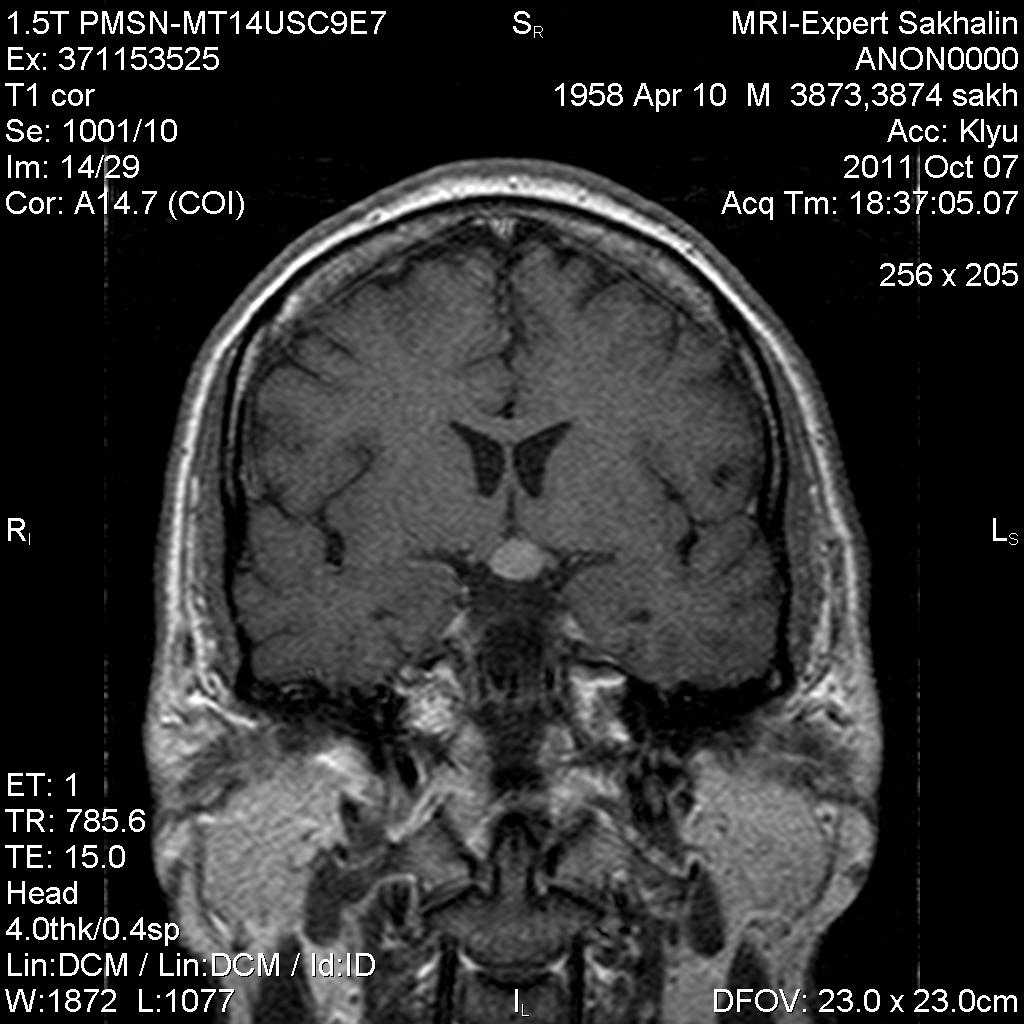

Аденома гипофиза

Вот такая аденома гипофиза сегодня.Мужчина с жалобами на снижение зрения.

Публикации: 175

Мне кажется что это все же не аденома, может глиома хиазмы ? (воронки гипофиза)? Или еще какое-нибудь объемное образование.... Что то меня смущает, еще не поняла что, но В любом случае наверное я бы однозначно не писала что это аденома, а выставила бы весь диф. ряд.

Танюша, обычно пишем "образование хиазмально-селлярной области"

Присоединяюсь к последнему коментарию, все таки откуда растет по моему мнению трудно однозначно сказать, лучше себя обезопасить написав "объемное образование хиазмально-селлярной области"